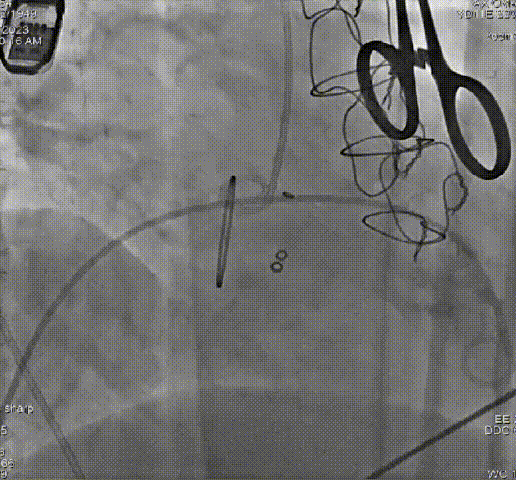

病例一

患者73岁,女性,“心房颤动”病史10年,4年前因“风湿性二尖瓣狭窄、冠心病”于心外科行“二尖瓣生物瓣置换术+三尖瓣成形术+冠脉旁路移植术”。近1年出现活动时气促,1个月来双下肢水肿。心脏超声:重度三尖瓣关闭不全,二尖瓣生物瓣位置及功能未见明显异常。TTVR术后三尖瓣关闭不全消失,无明显瓣周漏。

术前、术后造影结果